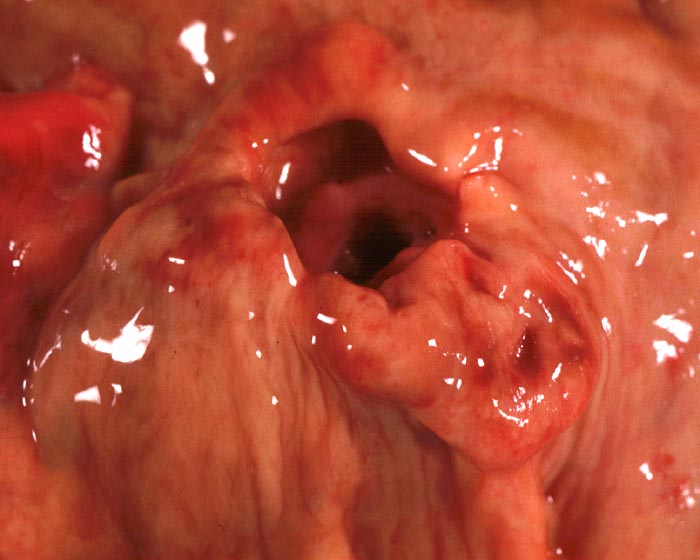

PathoPic – image database / PathoPic ID 2102 - Exulzeriertes neuroendokrines Karzinom

Exulzeriertes neuroendokrines Karzinom

Schüsselförmig exulzerierter Tumor mit aufgeworfenen verdickten Rändern.

Exulzeriertes neuroendokrines Karzinom des Magens (5x3x3cm) 3.5cm distal der

Cardia. Breitflächige Tumorinfiltration des

Pankreas mit Kompression des Pankreasganges. Metastasen in: Leber

(solitär Dm 2.6cm), Ovar links (Dm 8cm), periadrenalen

Weichteilen. Keine Lymphknotenmetastasen. C5:T4N0M1